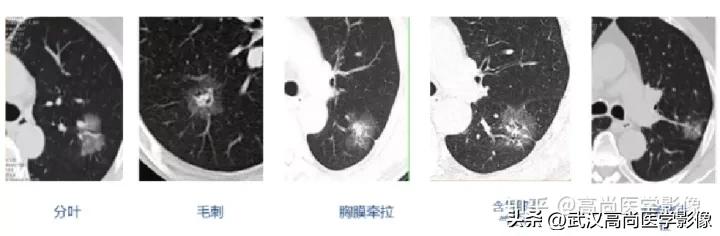

标准:直径≥15mm或表现出恶性CT征象(分叶、毛刺、胸膜牵拉、含气细支气管征和小泡征、偏心厚壁空洞)的直径介于8mm-15mm之间的肺实性结节。

恶性CT征象:

病灶边缘分叶、短毛刺,其近端亚段支气管截断,瘤肺界面清楚,病灶远端片絮状阻塞性炎症。

结节边缘不光整,分叶、长短不一的毛刺,邻近胸膜牵拉明显。